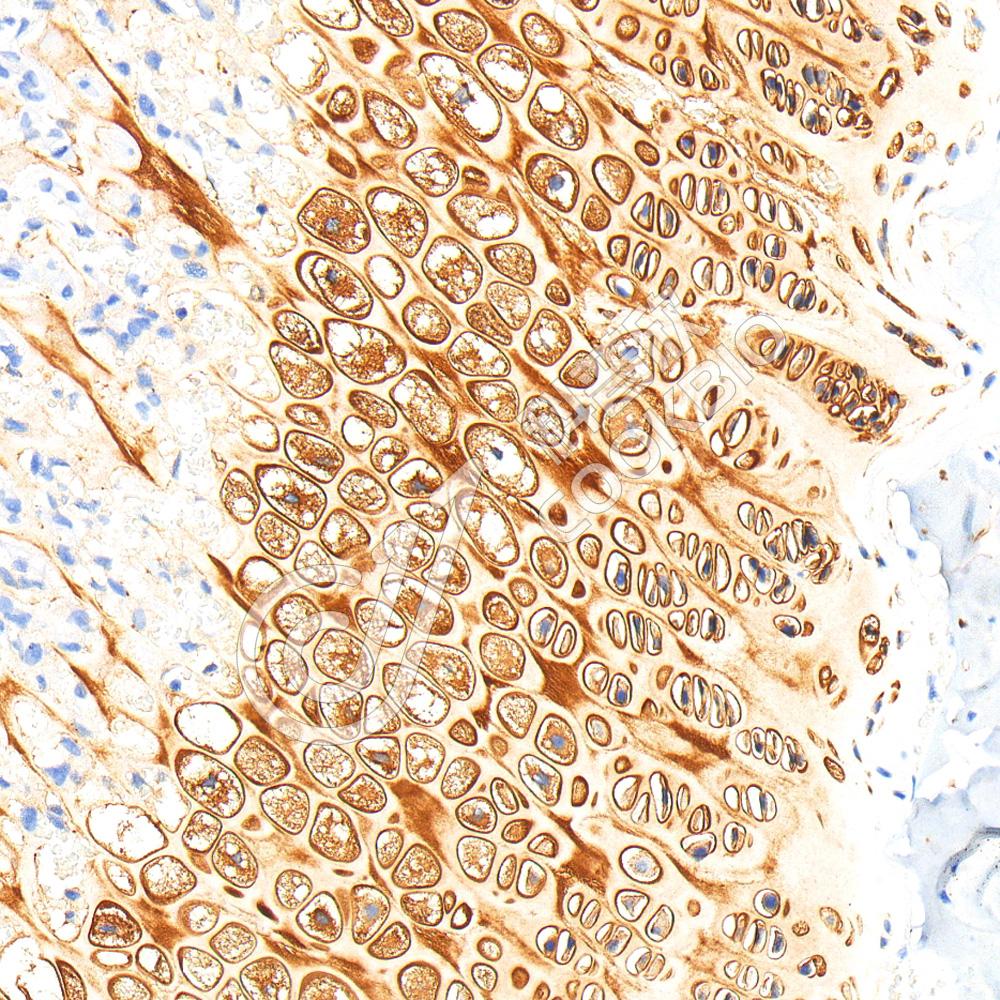

IHC检测Aggrecan蛋白(货号 K1347259).

样品: 小鼠软骨, 4%多聚甲醛 (货号KSG1101) 固定12-24小时.

抗原修复: 柠檬酸抗原修复液(干粉, pH 6.0) (KSG1201), 98℃, 20分钟.

—抗: 1: 800稀释, 4℃ 孵育过夜.

二抗: S-vision免疫组化多聚二抗(山羊抗兔),即用型 (货号KB3906), 室温孵育20分钟.

样品: 大鼠软骨, 4%多聚甲醛 (货号KSG1101) 固定12-24小时.